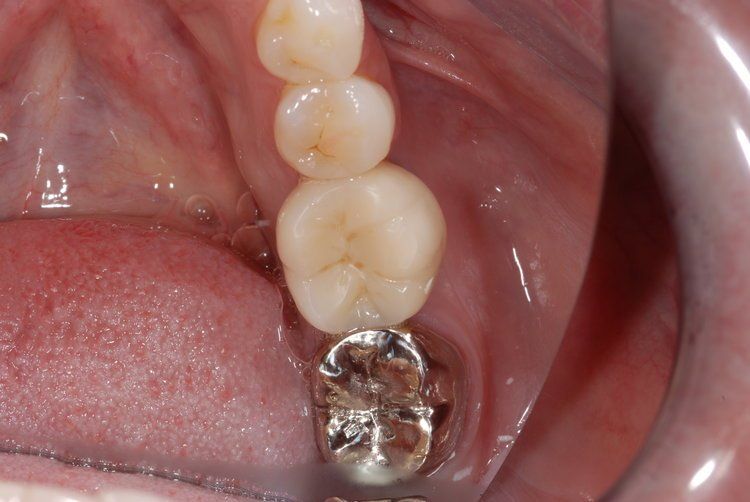

Unfortunately, it can be the case that a tooth (or teeth) are so badly damaged by trauma, bacteria, or tooth decay that removal is the only option. In this case, we recommend that a patient has dental implants inserted to replace any missing teeth. Modern dental implants are long lasting, strong, and look, feel, and function just like real teeth.

At the Dental Innovations clinic in Wasilla, AK, we specialize in single and multiple implant restorations. Our team can use a wide range of implant systems to provide patients with a full mouth of even, strong teeth. Contact our dental clinic today to arrange a consultation to discuss what dental implants may be the best for you.